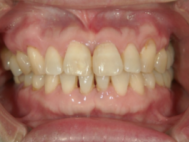

症例写真